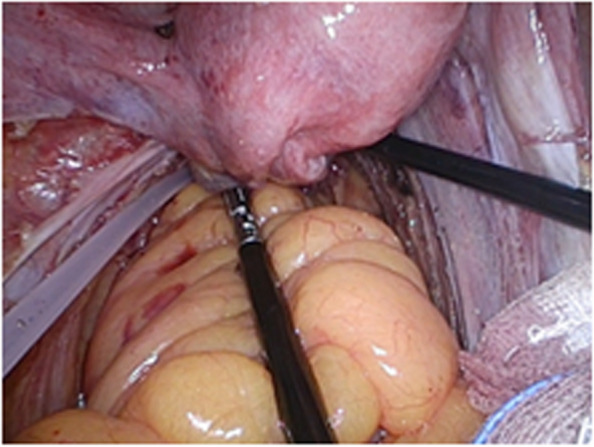

The fat flap containing ovarian vascular pedicle will be flipped downward and packed between the anastomotic stoma and vagina (9 o’clock to 3 o’clock of the outer wall of the rectum in lithotomy position), then fixed with medical fibrin glue. (Fig. 4)

Fig. 4.

The fat flap containing ovarian vascular pedicle packed between the anastomotic stoma and vagina, then fixed with medical fibrin glue